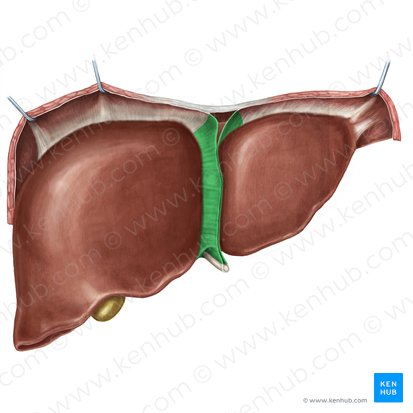

Right liver lobe

orange highlight

Left liver lobe

yellow highlight

Falciform ligament

Coronary ligament

Round ligament